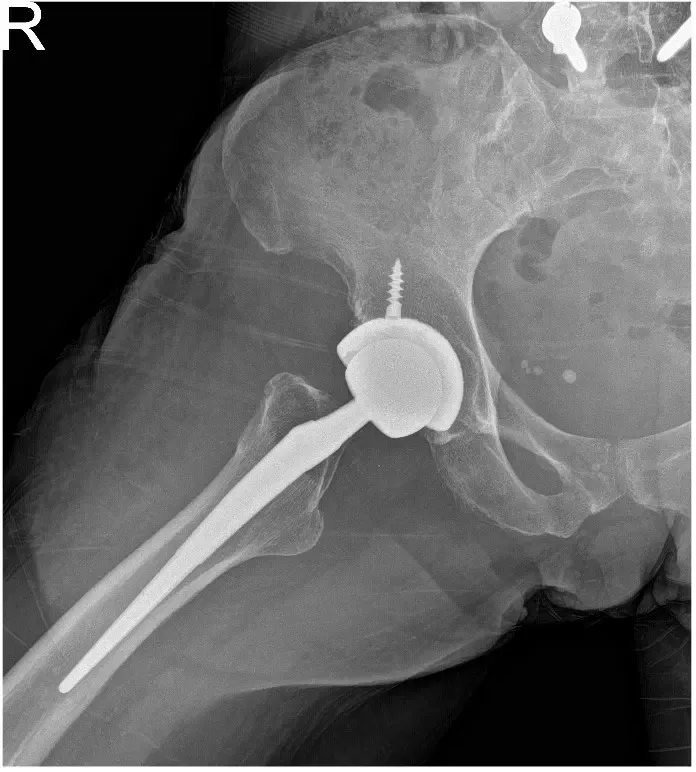

The remainder of the labrum was then removed. The acetabulum was sequentially reamed. The final shell was then placed into position in the correct abduction and anteversion. A screw was used for additional stability. A poly was placed over the shell. Attention was then turned towards the femur. The contralateral extremity was placed over a Mayo stand and the left lower extremity was placed in a figure of 4 position. The canal was sequentially broached.

The final broach was left into position. The trunnion and the head were placed over the broach. The hip was then reduced trialed through a full range of physiological motion and the hip was stable in all physiological range of motion. Fluoroscopy was obtained to ensure the correct length. Hip was dislocated. The trial components were then removed. Final components were then placed into position and the hip was then reduced. Thorough lavage was given. The wound was then closed in layers.

Similarly on the right hand side, a curvilinear incision was made. The patient was found to be stable to undergo a second hip replacement. The anterior approach was developed over to the right hip, though head of the femur was exposed in situ resection was made. The head was then removed. The acetabulum was then exposed. The labrum was then debrided. The acetabulum was sequentially reamed and the final shell was then placed into position in the correct abduction and anteversion.

A screw was used for additional fixation. The poly was then placed over the shell. The femur was then exposed after placing the contralateral extremity over the mayo stand and a figure of 4 position was used to broach the canal. Final broach was left into position. The head and trunnion were then placed over the broach and the hip was reduced. The hip was then trialed through a full range of physiological motion and the hip was stable through all physiological range of motion.

Fluoroscopy was carried out to ensure that both the limb lengths were equal. The trial components were then removed and the final components were placed into position and the hip was then reduced. Thorough lavage was given. The hip was then closed in layers. The patient was then transferred to the postoperative care unit in stable condition.